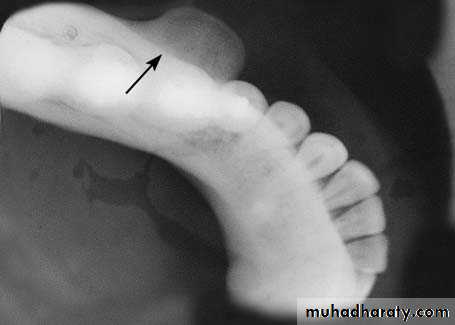

Protrusion of alveolar bone of the premaxilla after multiple extractions of anterior teeth

preprosthatic surgery

Supraeruption of maxillary teeth dragging down the alveolar ridge. Indication for alveoloplasty after extraction